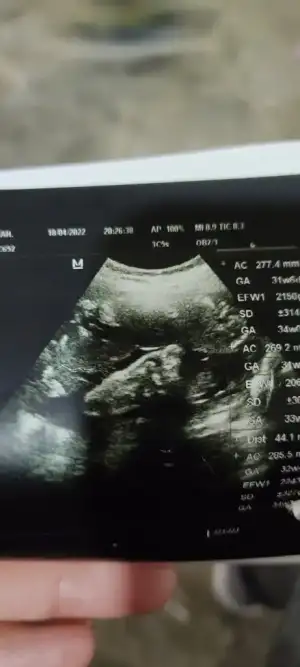

Kızlar doktordan geliyorum her şey normal ağrımın sebebi bu minik ayakcıkmış 😍

• IMG_20220418_212338.webp

IMG_20220418_212338.webp

20,6 KB · Görüntüleme: 57